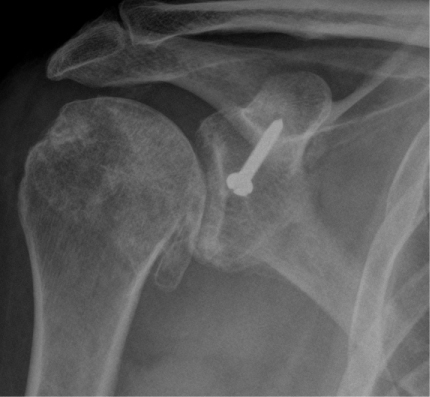

Anatomic Shoulder Replacement